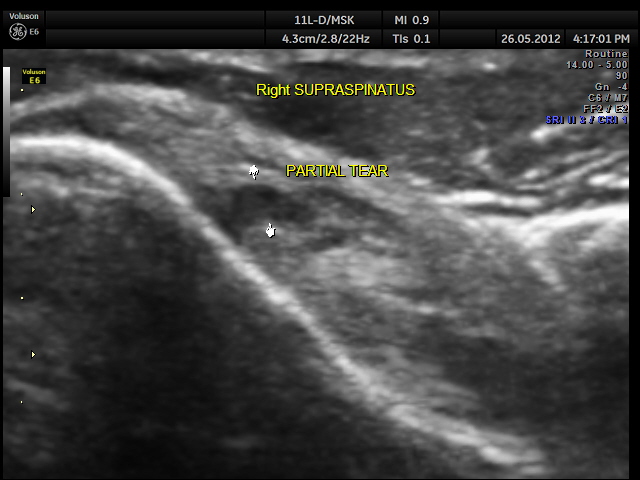

SUPRASPINATUS TEAR Date: May 27, 2012Author: kriznan Category: Shoulder, Musculo-skeletal ultrasound Tags: MUSCULO SKELETAL ULTRASOUND, PARTIAL TEAR, SHOULDER ULTRASOUND, SUPRASPINATUS TEAR Post navigation ← NON IMMUNE HYDROPS VESICAL CALCULI → This slideshow requires JavaScript.For imaging the rotator cuff, we need the high resolution transducer and appropriate positioning ; for the supraspinatus , I prefer the patient keeping his hand (of the side of the shoulder being examined ) in the opposite back pocket position Share this: Share on X (Opens in new window) X Share on Facebook (Opens in new window) Facebook Email a link to a friend (Opens in new window) Email Share on LinkedIn (Opens in new window) LinkedIn Share on WhatsApp (Opens in new window) WhatsApp More Print (Opens in new window) Print Share on Reddit (Opens in new window) Reddit Share on Tumblr (Opens in new window) Tumblr Share on Pinterest (Opens in new window) Pinterest Share on Telegram (Opens in new window) Telegram Like Loading...

extra ordinary clarity gives you the exact diagnosis. great skill